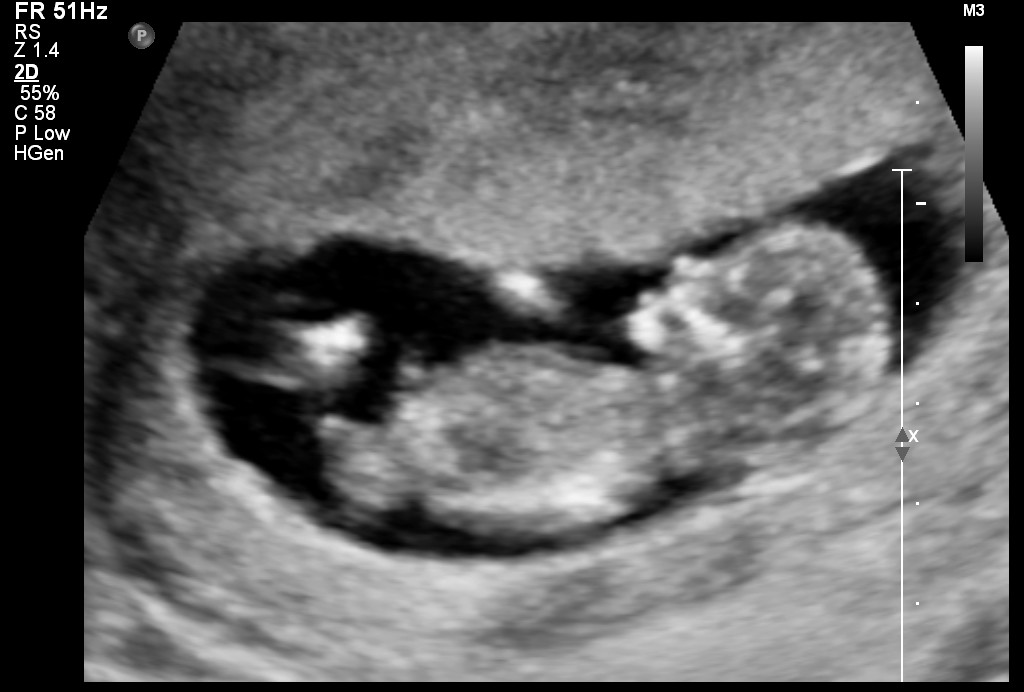

Any guesses would be appreciated :) Attachment 27980

Early but girly from me

Girlish Sent from my GT-I9305T using Tapatalk